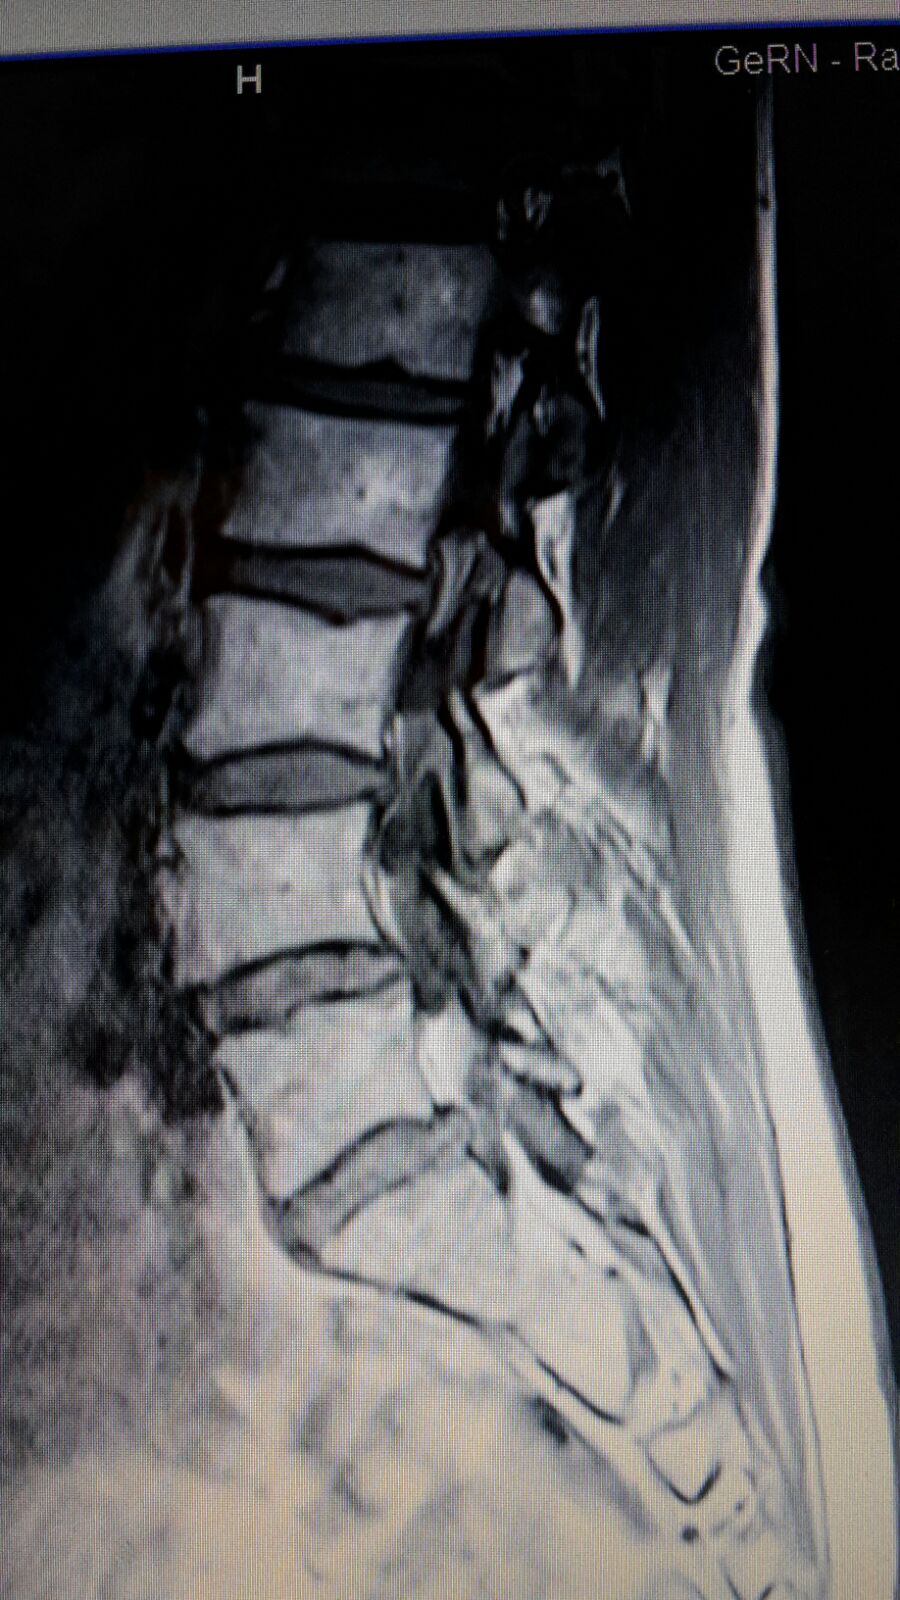

MRT Bilder LWS erste Einschätzung?

Wer kann mir etwas zu meiner LWS sagen? (Bandscheibenvorfall, MRT Befund)

Wer kann mir diese MRT Aufnahmen der LWS auswerten ? (Wirbelsäule, Befund)